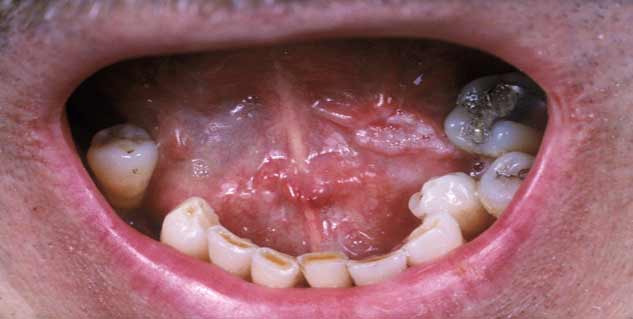

होठों, जीभ, गालों के अंदर की सतह पर या मसूड़ों में किसी प्रकार की गांठ कैंसर हो सकती है, इसे ओरल कैंसर कहते है। भारत में कैंसर से होने वाली मौतों में ओरल कैंसर एक बड़ा कारण है। इस बीमारी के कई मरीज जानकारी के अभाव और सही समय पर सही इलाज न मिलने के कारण मौत का ग्रास बन जाते हैं। ओरल कैंसर के इलाज में सबसे जरूरी है कि डॉक्टर पहले इस बात का पता लगाएं कि आखिर कैंसर किस स्तर तक पहुंच चुका है। अगर बीमारी गंभीर रूप धारण कर चुकी है, तो कई बार इसका पूरा इलाज संभव नहीं हो पाता।